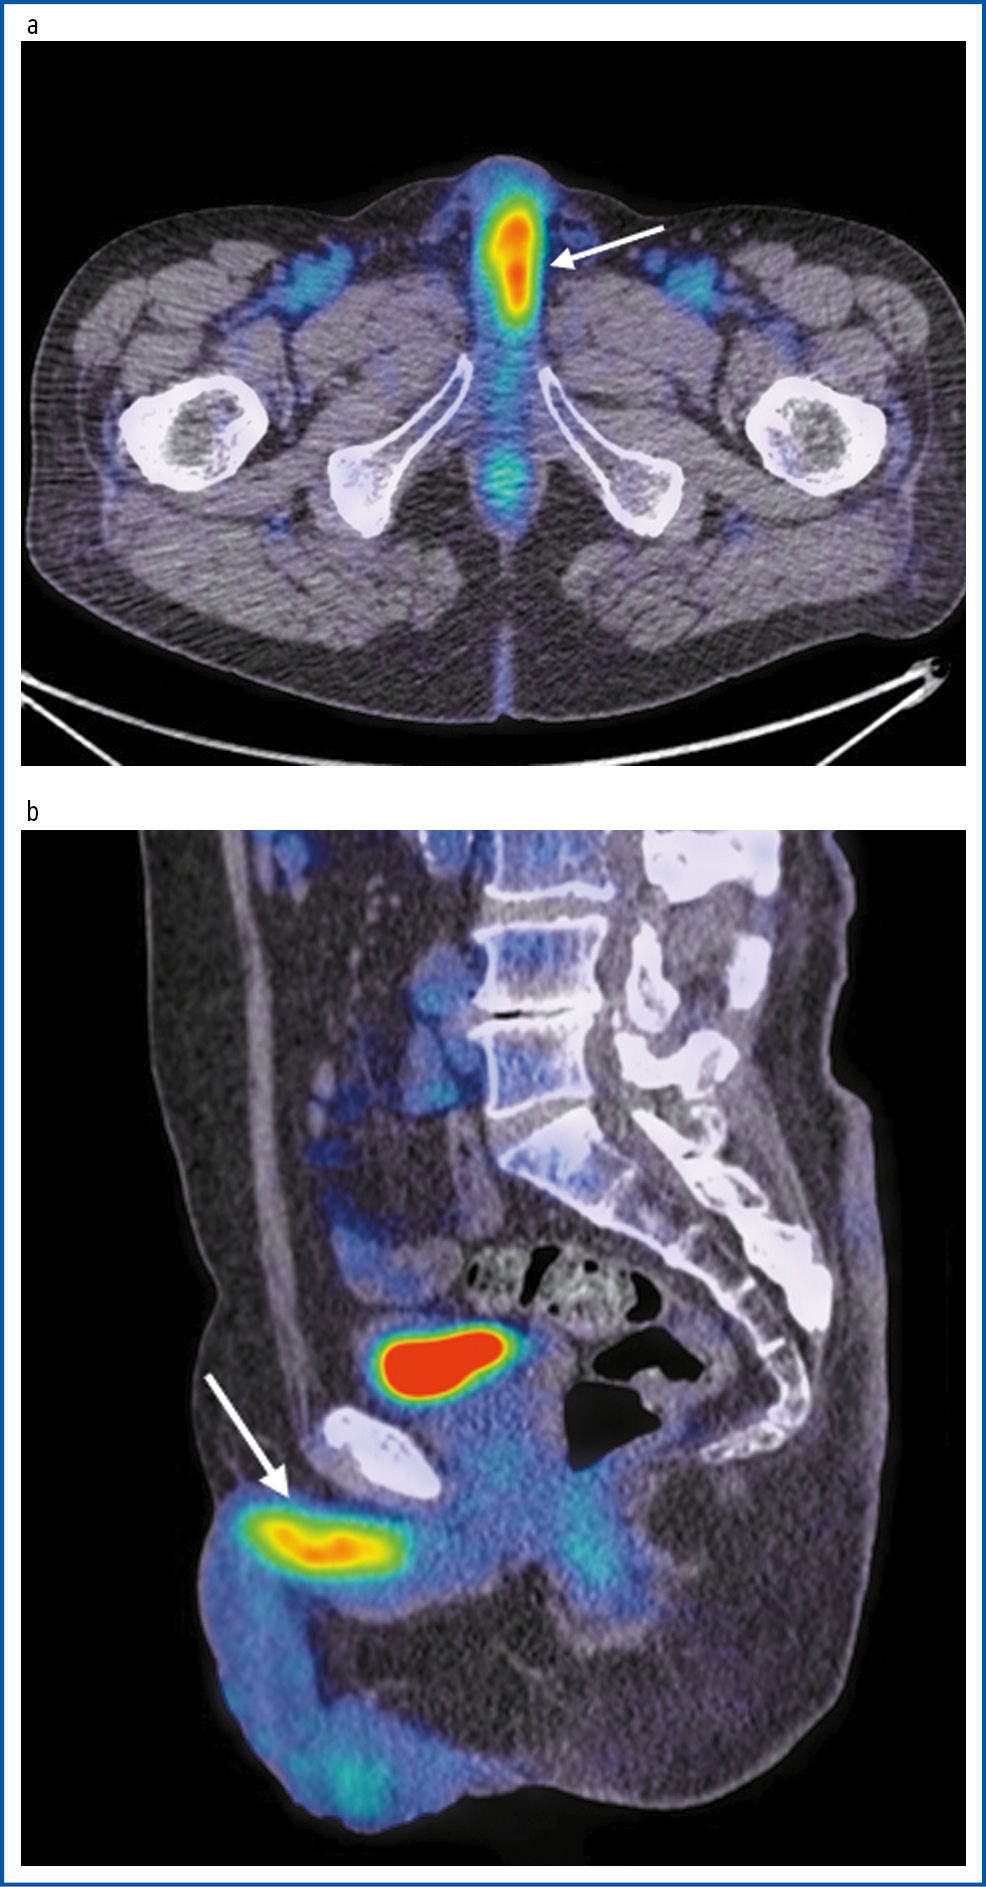

Для уточнения распространенности опухолевого процесса выполнена ПЭТ/КТ с 18-ФДГ. Выявлены специфические изменения в печени и ее воротах, внутригрудных, парааортальных, паракавальных лимфоузлах, ложе удаленного надпочечника и мягких тканях поясничной области. В пещеристых телах корня полового члена определяется образование без четких границ, размером 49×23×13 мм, коэффициент стандартизированного максимального накопления (SUVmax) радиофармпрепарата (РФП) равнялся 15,02. Заключение: прогрессирование опухолевого процесса; множественные метастазы в половой член, печень, лимфоузлы средостения, парааортальные и паракавальные лимфоузлы, рецидив в ложе удаленного надпочечника и мягких тканях поясничной области (рис. 2).

Рис. 2. Пациент Ф., 59 лет. На ПЭТ/КТ с 18-ФДГ в аксиальной (a) и сагиттальной (b) проекциях в корне полового члена определяется образование, размером до 49×23×13 мм с повышенной фиксацией РФП, SUVmax 15,02.

Fig. 2. Patient F., 59 years old. On PET/CT with 18-fluorodeoxyglucose in the axial (a) and sagittal (b) views in the root of the penis, a mass up to 49×23×13 mm with increased radiopharmaceutical uptake, SUVmax 15.02.

Величина SUVmax РФП в опухоли, по данным различных авторов, колеблется от 12,0 до 13,5 [19]. В литературе нет исследований, посвященных количественной оценке SUVmax как фактора дифференциальной диагностики первичного и вторичного рака полового члена.

По нашим данным, величина SUVmax в новообразовании составила 15,02.